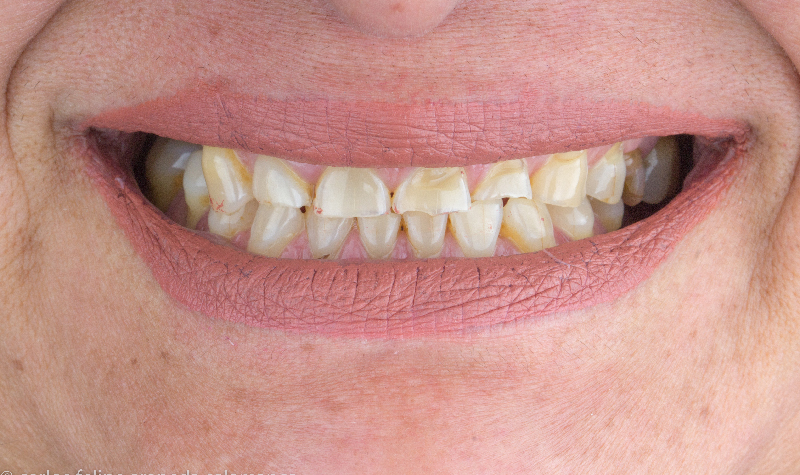

Diseño de Sonrisa Digital con carillas de cerámicas.